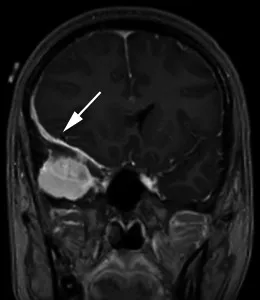

脑膜瘤MRI影像示例分析

案例二:35岁头痛女性患者。增强冠状位T1加权序列显示右中颅窝均匀强化轴外肿块,宽硬脑膜尾(箭头)沿蝶骨翼延伸,包绕右额叶外侧面。肿块导致大脑镰下向左移位7毫米,右侧脑室受压。术后病理证实为脑膜瘤(WHO 1级)。

案例六:70岁头痛女性患者。增强冠状位T1加权序列显示右中央前回受压(箭头),病灶轻度不均匀强化,宽基硬脑膜附着,周围显著血管源性水肿。T2加权序列呈高信号(与灰质对比)。术后病理证实为原发性乳腺癌腺癌转移。